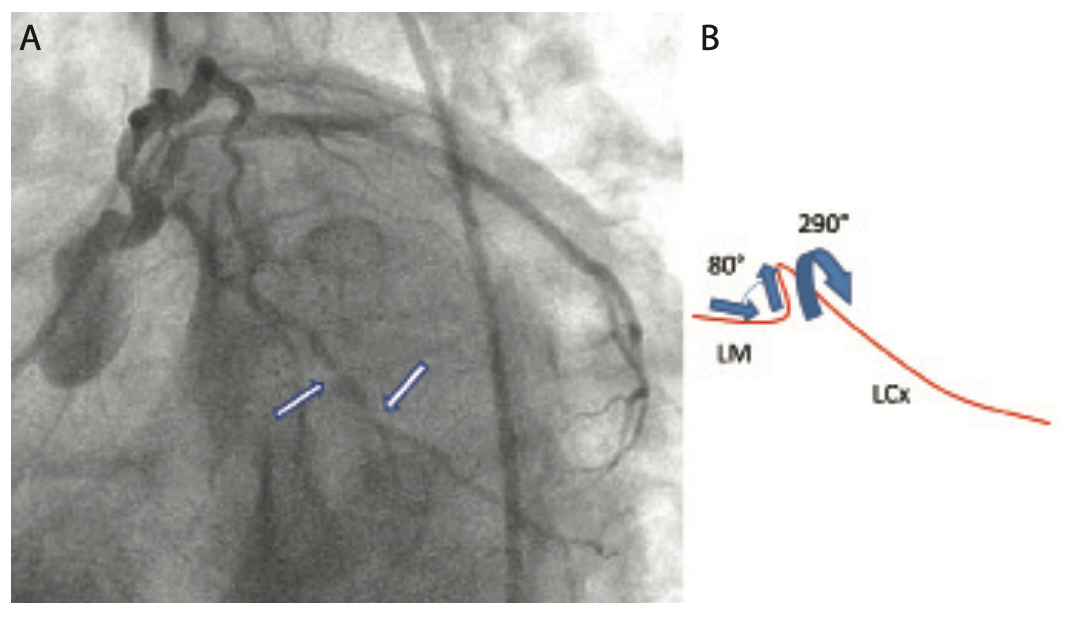

Given the anticipation for the need of significant support, this case was performed from a right common femoral artery access with a 6 French (Fr) extra backup (XB) 3.5 guiding catheter through a 6 Fr × 45 cm sheath. Figure 3 and Video 1 show a left anterior oblique (LAO) projection of the left coronary artery (LCA) system. The unusual aspect of the LCA anatomy is the tortuous mid left main (LM) segment approaching an 80° angle, which then gives rise to the left circumflex (LCx) artery at a very steep obtuse angle in the opposite direction. The addition of the two angles of the mid-LM tortuosity and the LCx artery takeoff comes close to 290°. This interesting anatomy, combined with the distal aspect of the LCx lesion extending to a small size third obtuse marginal branch (OM3), made this case relatively complex.